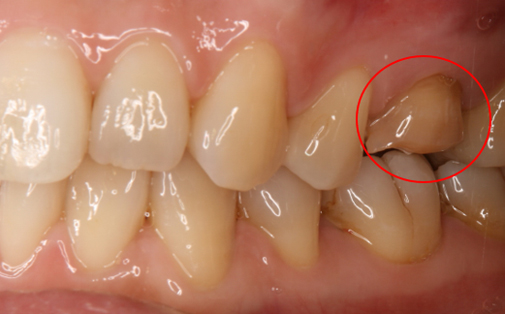

Before

After

左上の歯が折れています。折れた歯を抜き、親知らずの歯を移植しました。